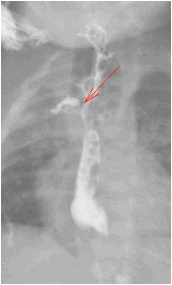

图 2 术后造影提示吻合口漏

2021-08-25 头颅超声:早产儿脑。CR 检查: 胸部 (正位), 腹部 (正位):食道闭锁术后:右侧胸壁皮下少量积气基本吸收;右肺上叶肺不张;新生儿肺炎较前稍吸收;肠管充气明显减少,建议随诊。CR 检查: 胸部 (正位), 腹部 (正位):食道闭锁术后:食道吻合口漏;右侧胸壁皮下少量积气基本吸收;右肺上叶肺不张,较前变化不大;右肺中野内带炎症较前加重。肠管充气少。

给予万古霉素抗感染治疗。9.5 腹部彩超:胃内可见少量内容物,余肠管肠腔萎瘪,走形迂曲;腹腔未见明显肠套叠、肠梗阻及阑尾炎征象。9.13 食管造影:食道闭锁术后改变,吻合口漏。贲门位置抬高,建议随诊肺炎。2021-09-28 造影检查: 食管造影:食道闭锁术后改变,吻合口漏,较前稍好转。贲门位置抬高,建议随诊;肺炎;先天性心脏病。磁共振检查 (1T 以上不含 1T): 颅脑 (磁共振功能成像, 平扫):早产儿脑,左侧侧脑室后角室管膜下局灶性脑损伤,小脑幕缘硬膜下少量出血。